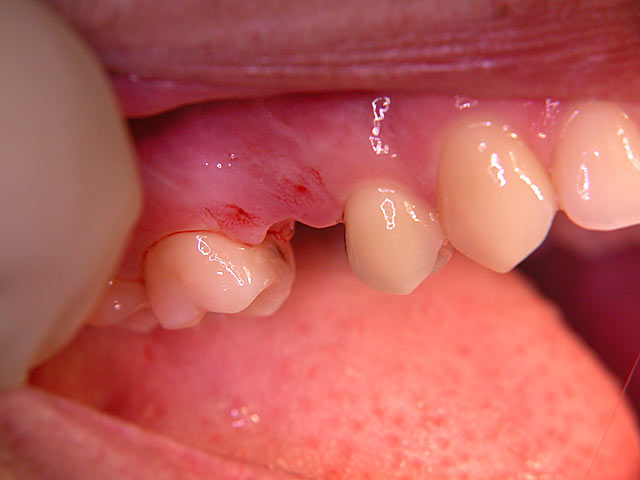

Die folgenden Patientenfälle sollen Ihnen einen Einblick in die Möglichkeiten der modernen Implantation geben.

Implantation mit Knochenblock-Implantaten: